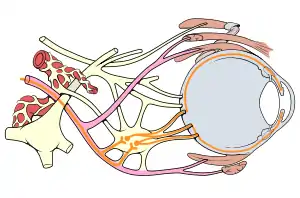

| Eye nerves diagram | |

Mechanism

As the pair of oculomotor nerves arises from different subnuclei in the midbrain, courses through different structures in the brain and branches into superior and inferior divisions after exiting the cavernous sinuses, any lesions along its path will produce different pathological features of the third nerve palsy. The parasympathetic aspect of the nerve (which constricts pupils and thicken the lens) is located on the nerve surface, supplied by pial blood vessels. The nerve's core contains the main trunk of the oculomotor nerve, supplied by vasa vasorum. Thus pathologies affecting the nerve's core without affecting the superficial part of the nerve (thus sparing the pupillary reflex) are known as "medical" oculomotor nerve palsy. The "surgical" type of oculomotor nerve palsy is caused by external structures compressing on the nerve or trauma, which affects the entire nerve, thus affecting pupillary reflex.[2]

Ischemic stroke selectively affects somatic fibers over parasympathetic fibers, while traumatic stroke affects both types more equally. Ischemic stroke affects the vasoneurium, which starts to supply the nerve from outside to inside. As the somatic fibers are located in the inner part of the nerve, these fibres are affected more in the setting of ischemia. A similar mechanism is also accurate for diabetes. Therefore, while almost all forms cause ptosis and impaired movement of the eye, pupillary abnormalities are more commonly associated with trauma and the "surgical third" rather than with ischemia (the "medical third"). A posterior communicating artery aneurysm will generally cause compression of the entire third nerve and will this prevent any nerve signal conduction, affecting the somatic system as well as the autonomic. The compression of the external autonomic fibres renders the pupil nonreactive and leads to the "surgical third" nerve palsy.